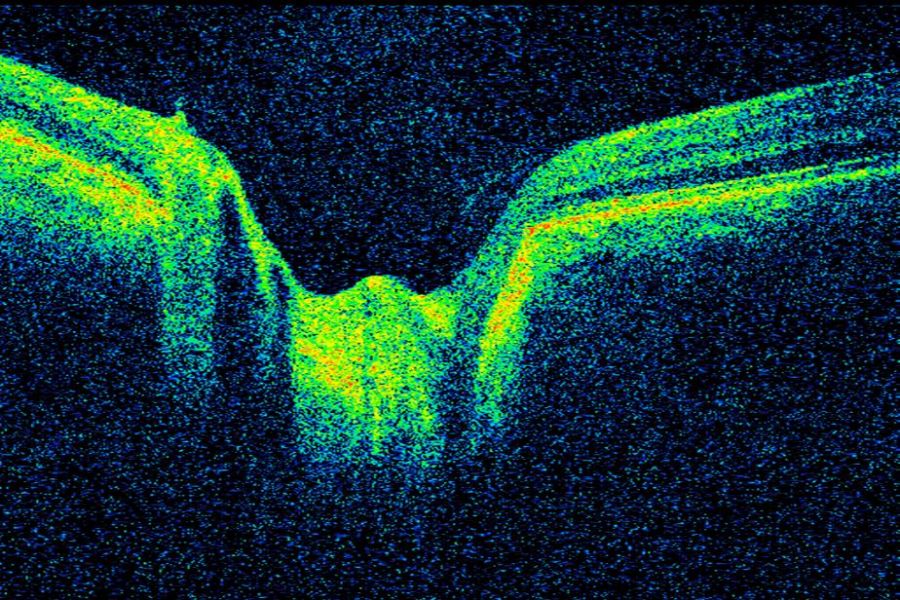

Grubenpapille (siehe Anmerkung)

Papillengrube (аббревиатура: Grube)